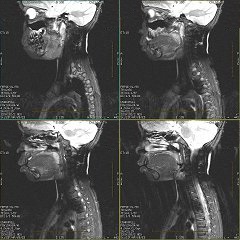

Figure 2. Sagittal FRFSE-XL images displaying poor uniformity fat SAT